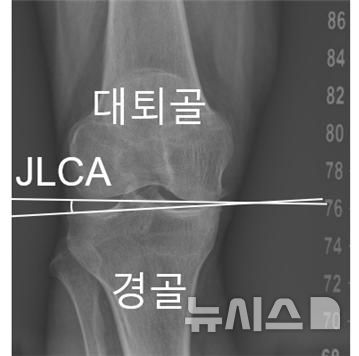

[서울=뉴시스] 무릎 관절선 수렴각(JLCA). (사진= 서울대병원 제공)

연구팀은 무릎 관절을 이루는 대퇴골과 경골 사이의 관절선이 벌어진 정도인 '관절선 수렴각'이 이러한 가속 진행을 예측하는 공통 지표임을 밝혀냈다. 초기에 측정된 JLCA가 1도 커질 때마다 O자형 환자에서 12.9%, X자형 환자에서 19.4%씩 가속 진행 위험이 증가했다.